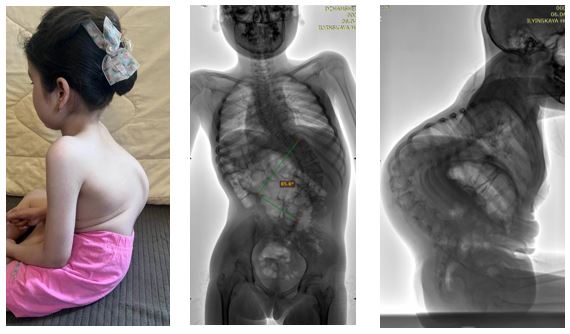

Недавно в один день двумя хирургическими бригадами в соседних операционных были прооперированы родные сёстры — 12 и 8 лет — с тяжёлым генетическим заболеванием, спинальной мышечной атрофией.

При подобных заболеваниях деформация позвоночника прогрессирует значительно быстрее и протекает тяжелее, чем при обычном идиопатическом подростковом сколиозе. Искривление влияет не только на внешний вид, но и на:

• способность удерживать тело в вертикальном положении (в первую очередь — возможность сидеть);

• работу сердечно-сосудистой и дыхательной систем;

• переносимость реабилитационных мероприятий;

• качество жизни ребенка и ухода за ним.